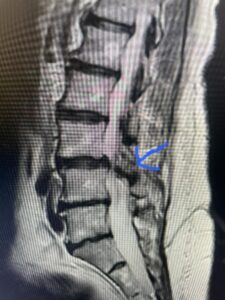

Another patient is a 62 year-old female with progressive low back pain and right leg pain and numbness that radiates to the top of her foot. She tried physical therapy and epidural injections. MRI demonstrated severe L3-4 stenosis and a grade 1 spondylolisthesis (Fig 4). There was L5-S1 and L4-5 disc collapse with modic end-plate changes. Biomechanically because of the significant degeneration of these disc spaces which stiffened the L4-S1 segment more stress was placed on the L3-4 segment, resulting in significant premature degeneration and compensatory stenosis and segmental instability. The MRI also showed pathologically, because of the slip, the L3 inferior processes were more anteriorly oriented and hence contributing to the majority of the lumbar canal compromise. Note the more sagittally-oriented facets in this case compared to the prior case (Fig 5). The patient underwent a decompressive laminectomy with attention of removing the inferior processes of L3 to fully decompress the canal. We also performed an L3-4 fusion with instrumentation (Fig 6). The patient had an uneventful postoperative course with improvement of leg pain. Of note with relief of the disabling leg pain patients are generally very happy. Patients can often manage their low back pain; it is the leg pain that they just can’t tolerate.

Fig 4: Sagittal T2-weighted lumbar MRI demonstrating L3-4 grade 1 spondylolisthesis with severe stenosis (blue arrow)

Fig 5 Axial T2-weighted lumbar MRI demonstrating significant L3 inferior facet contribution of severe stenosis (blue arrow)